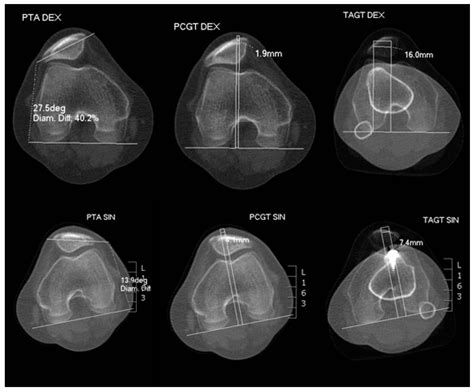

• Imaging Studies: X-rays, MRI, and CT scans can provide detailed images of the knee joint, helping to identify any structural abnormalities, fractures, or soft tissue injuries. MRI is particularly useful for visualizing the MPFL and other ligaments.

• Tibial Tubercle Osteotomy: This procedure involves realigning the patellar tendon by moving the tibial tubercle (the bony prominence on the tibia where the patellar tendon attaches). It is often performed in conjunction with MPFL reconstruction to address underlying malalignment issues.